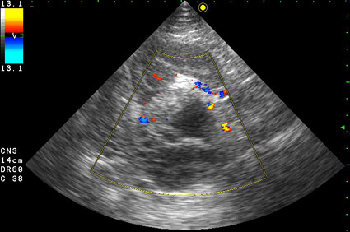

- Образование в режиме ЦДК.